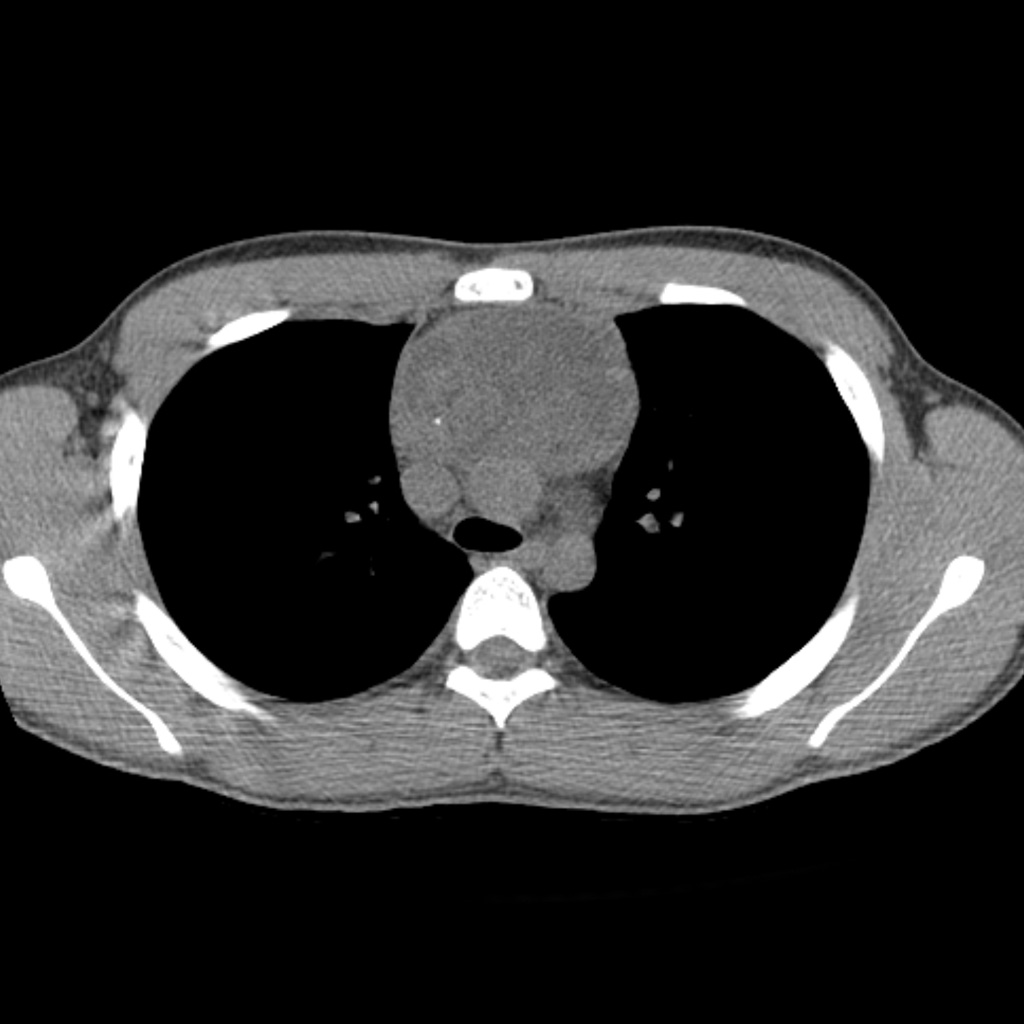

Рентгеновские снимки тератомы средостения: Диагностика и лечение

Раздел: Фотоэссе